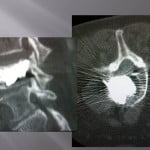

Vertebroplasty technique for vertebra-plana.

The position of the patient in hyperlodosis in order to reduce the fracture and increase the intra-somatic space is important. We systematically perform a extra-pedicular access or intercosto-vertebral access so that the trocar as more mobility in the vertebrae. The progression of the trocar is performed under scopic guidance, the penetration must be strictly intra-corporeal in the same axis as the fracture. A scanner control confirms the position in the fractured zone, the bevel of the trocar is oriented toward the important residual bone surface. We fill a first part of the vertebrae with a few drops of liquid cement to judge and anticipate the positioning and the frequent discal leaks. Under continual scopy, we visualize a linear diffusion intra-vertebral of the cement. Then we wait a few minutes to allow polymerization and get a high viscosity cement that we will push slowly in the cannula with a needle. The large viscosity at the end of the procedure is a key element to the correct filling of these fractures. The injection can be performed by filling the canulae and pushing the cement with the trocar. In case of a cement that is too liquid and a too large pressure applied at the point of intra-corporeal injection, the cement comes back up in the perforated needle to limit the risk of leaks at the epidural level. A thick and old cement diffuses close to the distal end of the trocar. Similarly the progressive retreat of the trocar by pushing to the needle the rest of the cement allows for perfect cementing in the rest of the way.

The subchondral space must be perfectly filled, the pressure in this space being smaller, the diffusion is easy. Also, a gain in height is frequently observed in this type of lesions. The post-operation precautions are the same as for osteoporotic fractures.